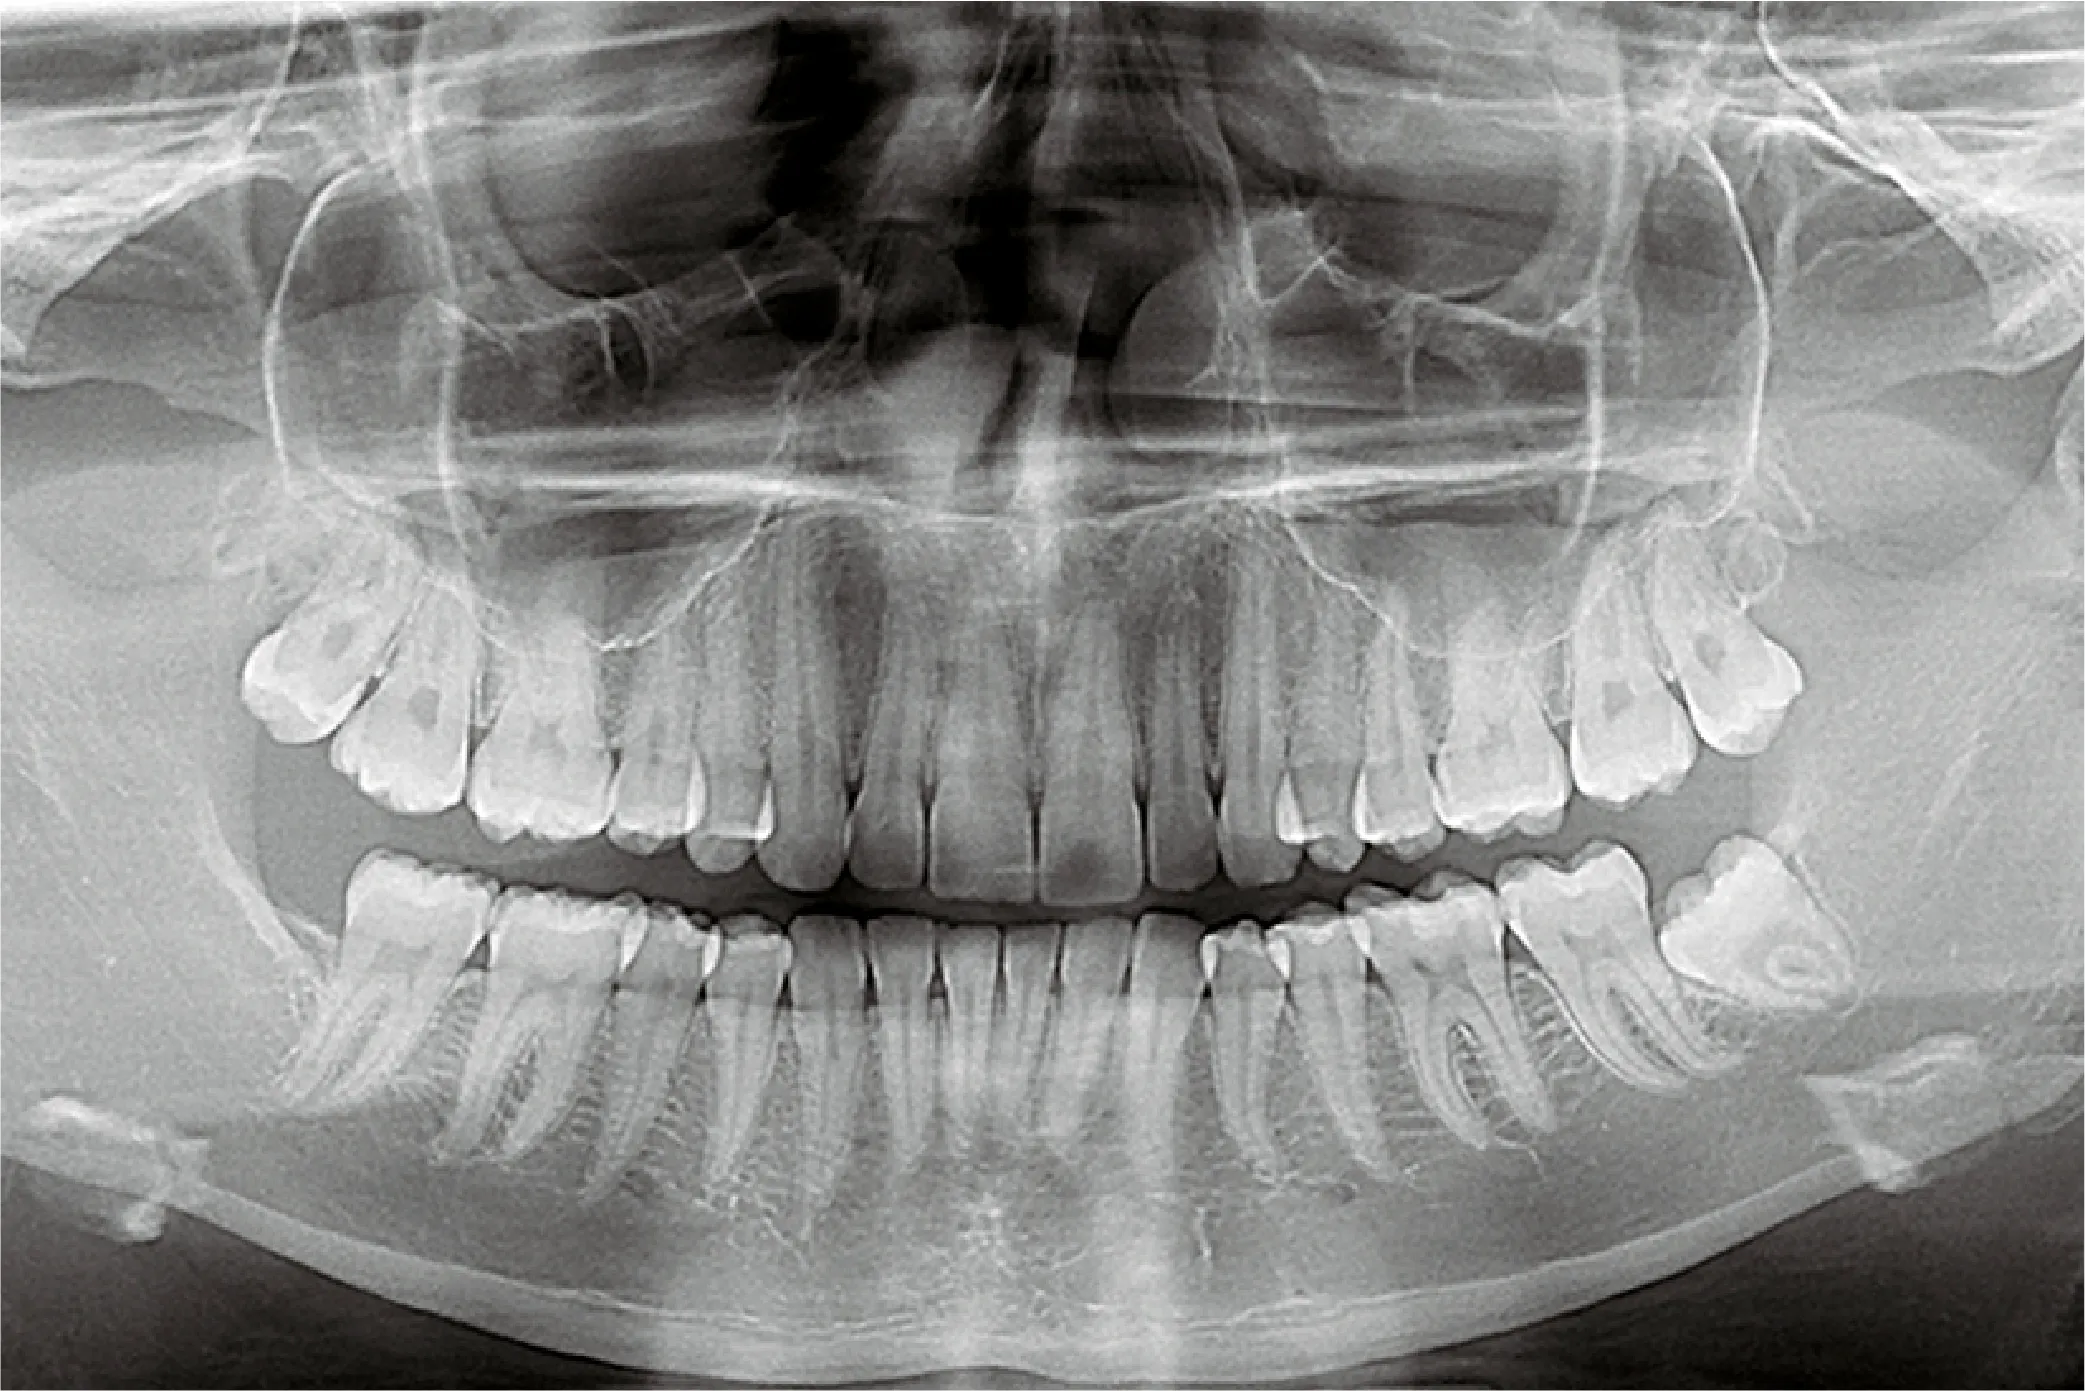

Providing detailed images of the body using technologies such as X-ray, MRI, CT scans, and ultrasound to aid in the diagnosis of various medical conditions.